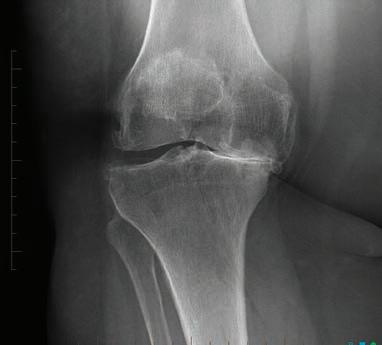

Perth Radiological Clinic’s MSK sub-specialist team

At Perth Radiological Clinic your musculosketal (MSK) investigations are reported locally by Perth’s largest team of musculoskeletal and spinal radiology experts.

• Rapid access to high quality scans and image guided injections.

• MRI appointments available evenings and weekends.

• Fast report turnaround times delivered by Perth’s largest team of musculoskeletal and spinal radiology experts.

• Radiologists available to discuss the imaging and interventional requirements

PRC MSK sub-specialist, Dr Matt Prentice saysOur rapid turnaround reports expedite the path to appropriate treatment, can rule out serious pathology or help differentiate acute injury from chronic non traumatic conditions.

Please contact your customer relations team for more information or email assist@perthradclinic.com.au